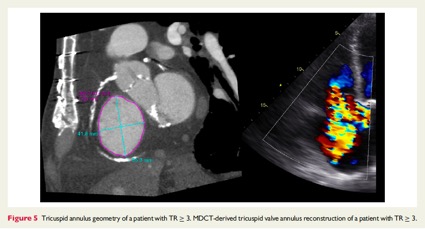

二つ目は前回も紹介した私の論文のsupportをしてくれているPhilippeの論文です。

文献6: van Rosendeal PJ, et al. Eur Heart J Cardiovasc Imaging 2016;17:96-105.

CTによるTricuspid valve remodelingの解析とTRに対する影響に関して述べています。3年前の論文ですが、私がMultimodality imagingの重要性を学んだ論文の一つでもあります。

Figure 6(図6: 文献6より引用)